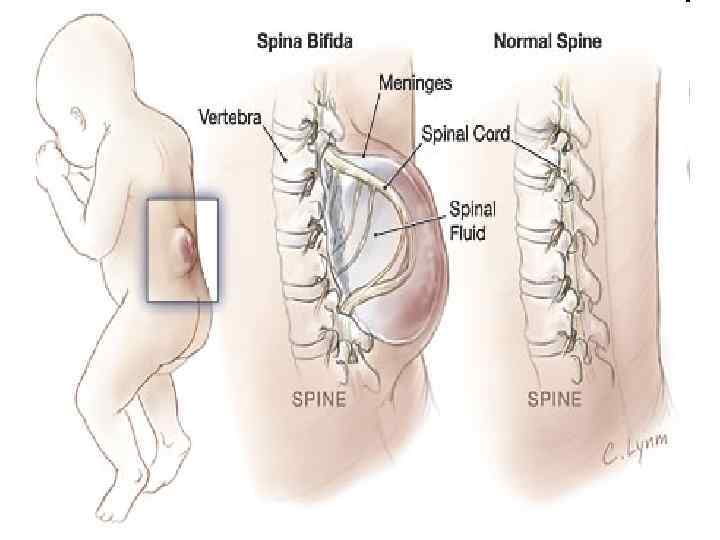

SPINA BIFIDA 111

Менингорадикулоцеле 112

Менингомиелоцеле 113

114

115

Ребенок со spina bifida 116